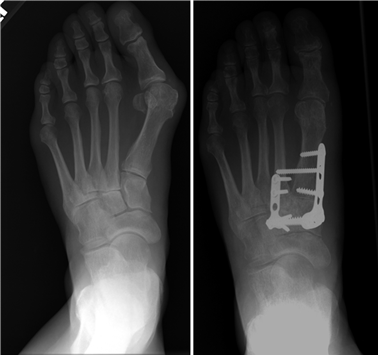

When conservative measures fail, the choice of procedure is dictated by the severity of the deformity, the presence of degenerative joint disease, and the stability of the first TMT joint. Distal osteotomies (e.g., Chevron) are generally reserved for mild to moderate deformities with an intermetatarsal angle (IMA) less than 13 degrees. Diaphyseal osteotomies (e.g., Scarf) offer greater translational correction for moderate to severe deformities. Proximal procedures, such as the Lapidus arthrodesis, are indicated for severe deformities (IMA > 15 degrees), clinical hypermobility of the first TMT joint, or recurrent hallux valgus. For hallux rigidus, joint-sparing procedures like cheilectomy are indicated for early-stage disease, while first MTP arthrodesis remains the gold standard for end-stage arthritis.

Weight-bearing anteroposterior (AP), lateral, and sesamoid axial radiographs are mandatory. On the AP view, the surgeon measures the Hallux Valgus Angle (HVA, normal < 15°), the Intermetatarsal Angle (IMA, normal < 9°), and the Distal Metatarsal Articular Angle (DMAA). The lateral view is scrutinized for Meary's angle (talo-first metatarsal angle) to identify midfoot collapse, as well as the presence of dorsal osteophytes indicative of hallux rigidus. The sesamoid axial view is critical for assessing the degree of sesamoid subluxation and the integrity of the crista.